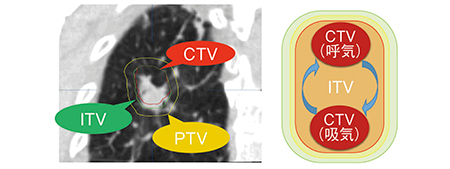

呼吸性移動を伴う臓器の腫瘍に対する放射線治療では,移動量を正確に把握する必要がある。そこで,臨床標的体積(clinical target volume:CTV)に加えて,臓器の動きの影響を含めた内的標的体積(internal target volume:ITV)を評価する(図2)。ITVの評価には一般的に4D-CT,X線透視撮影,シネMRIが用いられるが,従来装置の4D-CTでは,動きによるアーチファクトが多く,腫瘍の同定や移動量の評価が困難であった。4D-CTでは,92%の患者において何らかのアーチファクトが発生するという研究結果も示されている1)。その要因は,患者の呼吸を正確にとらえられないためであると指摘されており,当クリニックにおいても,従来装置ではオーバーラッピングのようなアーチファクトが発生していた。しかし,同一症例をRT Pro editionで撮影すると,横隔膜周囲のアーチファクトが劇的に改善されていることがわかる(図3)。

図2 呼吸性移動を考慮したITVの設定